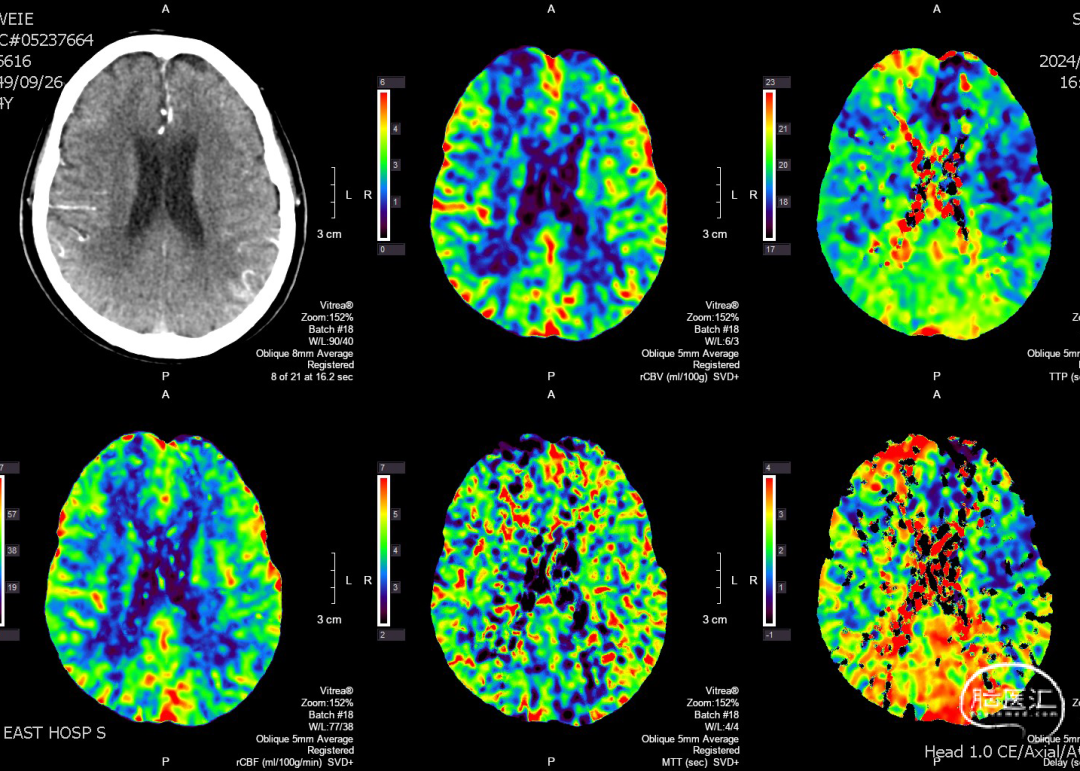

现病史:患者2024.6.6 15:00突发言语不利伴右侧肢体活动障碍,17:00就诊于急诊神经内科,行头颅CT未见出血,立即予以静脉溶栓治疗后症状未缓解。完善头颅CTP提示左侧大脑中动脉M2段狭窄,为责任血管,存在低灌注区,附见一动脉瘤。

术前CTP

复查CT及CTP:未见出血及低灌注区。